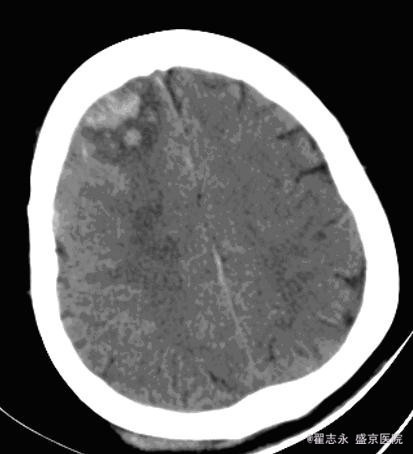

肝炎后肝硬化失代偿期并发脑出血

患者女,55岁。丙肝后肝硬化,全血细胞减少,白细胞计数,2.7*10^9/L,血红蛋白,54g/L,血小板计数,5*10^9/L。突然出现头痛。

2小时后突然意识不清,考虑再出血。后死亡。

脑内出血的可能病因有高血压、动脉瘤、动脉硬化、脑动脉淀粉样变性、动静脉畸形、血液病等。 肝炎后肝硬化失代偿期并发脑出血, 临床症状多不典型, 如果不及时进行仔细检查, 易误诊为肝性脑病或电解质紊乱。肝硬化失代偿期并发脑出血, 发病前无前驱症, 病情进展迅速, 突然发生意识障碍, 出血量大, 病情危重, 病死率高。 发病机制, 可能与下列因素有关: 1、肝炎后肝硬化失代偿期肝功能贮备能力下降, 维生素K 吸收差, 凝血因子和凝血酶原合成障碍, 导致凝血功能下降。2、肝炎后肝硬化失代偿期大多数有脾功能亢进, 继发性血小板减少。3、肝炎后肝硬化失代偿期继发性醛固酮增高, 出现高醛固酮血症, 导致水、钠储留, 器官血流量增加, 内脏血管及全身血管扩张, 处于高动力循环状态, 血管承受的压力大, 易导致脑血管破裂。4、毛细血管脆性增加。 血液病所致脑出血,多位于脑皮层,可能为多处。且血肿不均匀。在血液病未纠正情况下,极容易再出血,再出血量大,死亡率高。